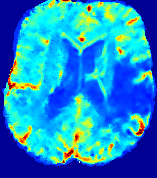

LesionRefer to captionRefer to captionRefer to captionRefer to captionRefer to captionRefer to caption𝐕rgbsubscript𝐕𝑟𝑔𝑏{\bf{V}}_{rgb}Refer to captionRefer to captionRefer to captionRefer to captionRefer to captionRefer to caption𝐕2subscriptnorm𝐕2{\|\bf{V}}\|_{2}Refer to captionRefer to captionRefer to captionRefer to captionRefer to captionRefer to captionRefer to caption3.53.53.52.82.82.82.12.12.11.41.41.40.70.70.70.00.00.0(mm/s)𝑚𝑚𝑠(mm/s)D𝐷DRefer to captionRefer to captionRefer to captionRefer to captionRefer to captionRefer to captionRefer to caption0.0200.0200.0200.0160.0160.0160.0120.0120.0120.0080.0080.0080.0040.0040.0040.0000.0000.000(mm2/s)𝑚superscript𝑚2𝑠(mm^{2}/s)Slice #1Slice #2Slice #3Slice #4Slice #5Slice #6

Figure 3: PIANO feature maps for one stroke patient, where the lesion is located in the left hemisphere. Top row: segmented stroke lesion region (white) on different slices, obtained from ISLES 2017. The corresponding slices for the PIANO feature maps are shown in the following rows.

For a better insight into an estimated velocity field 𝐕𝐕{\bf{V}} and diffusion field 𝐃𝐃{\bf{D}}, we compute the following maps: (1) 𝐕rgbsubscript𝐕𝑟𝑔𝑏{\bf{V}}_{rgb}: Color-coded orientation map of 𝐕=(Vx,Vy,Vz)T𝐕superscriptsuperscript𝑉𝑥superscript𝑉𝑦superscript𝑉𝑧𝑇{\bf{V}}=(V^{x},V^{y},V^{z})^{T}, obtained by normalizing 𝐕𝐕{\bf{V}} to unit length and mapping its 3 components to red, green, blue respectively; (2) 𝐕2subscriptnorm𝐕2\|{\bf{V}}\|_{2}: 222 norm of 𝐕𝐕{\bf{V}}; (3) D𝐷D: scalar field in Eq. 5.

Fig. 3 and Fig. 4 show the PIANO feature maps estimated from two ISLES 2017 patients: all are highly consistent with the lesion in both cases. Details of the blood flow trajectories are revealed in 𝐕rgbsubscript𝐕𝑟𝑔𝑏{\bf{V}}_{rgb} by the ridged patterns and the sharp changes of colors in the unaffected (right) hemisphere, while the flat patterns appearing within the lesion provide little directional information about the velocity and indicate low velocity magnitudes. Velocity magnitudes are more directly visualized via 𝐕2subscriptnorm𝐕2\|{\bf{V}}\|_{2}, from which one can easily locate the lesion where 𝐕2subscriptnorm𝐕2\|{\bf{V}}\|_{2} is low. D𝐷D also indicates lower diffusion values in the lesion, though with less contrast potentially due to the fact that it captures the accumulated effect of CA diffusion at the voxel-level.